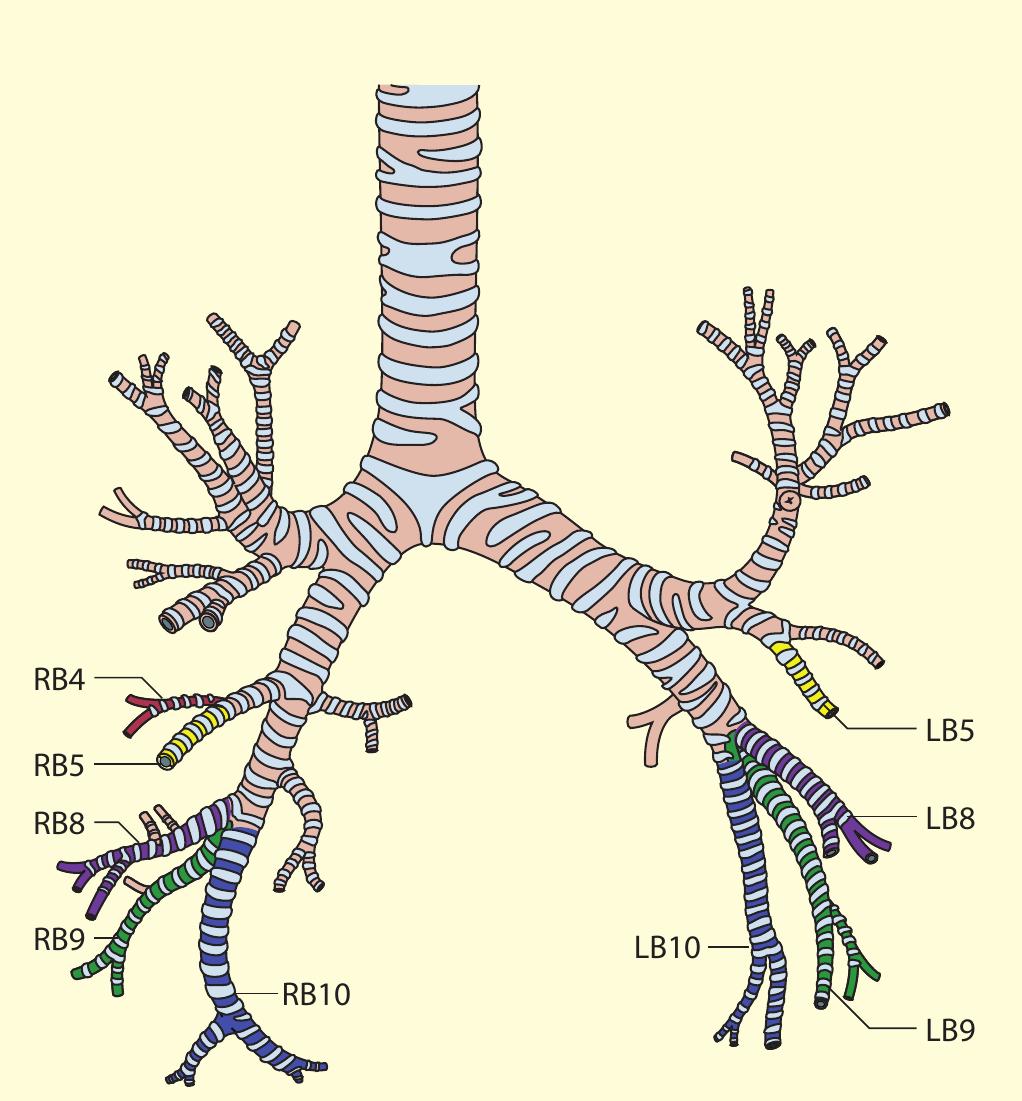

- Our approach, for example, for the right lower lobe is to treat RB10 (right posterior basal bronchus) first, using the BF260 bronchoscope (external diameter 4.3 mm) so that the distal subsegments can be assessed.